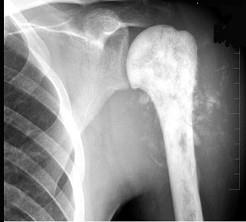

问题 28岁男性患者,右肱骨上段肿痛1个月,疼痛以夜间明显,摄片如图所示,提示骨肉瘤最为主要的征象是 ( )

选项 A、软组织肿块影 B、骨膜增生 C、肿瘤骨形成 D、溶骨性破坏

答案 C